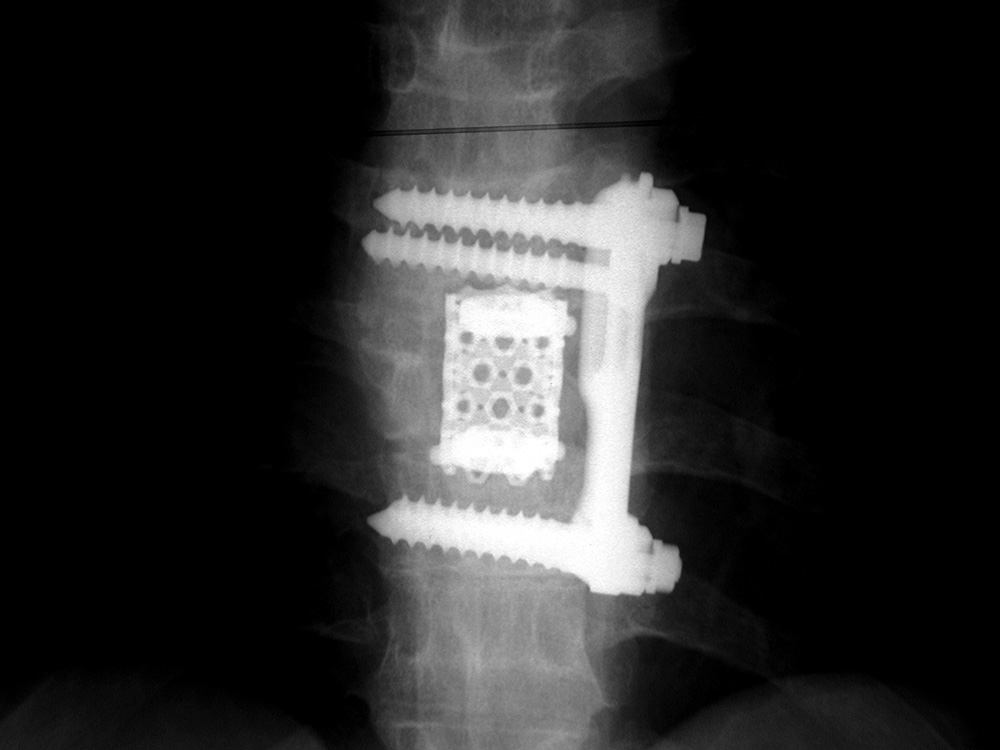

Anterior cage dislodgement in posterior lumbar interbody fusion a

Anterior cage dislodgement in posterior lumbar interbody fusion a How Long Does Spinal Cage Surgery Take In an interbody spinal fusion, the damaged intervertebral disk is removed and replaced with bone graft material. Connecting them prevents movement between them. This depends upon your individual situation including how many of the vertebrae are fused and the extent of the damage. Physical therapy helps regain strength and mobility of the muscles of the lower back. Recovery from spinal. How Long Does Spinal Cage Surgery Take.